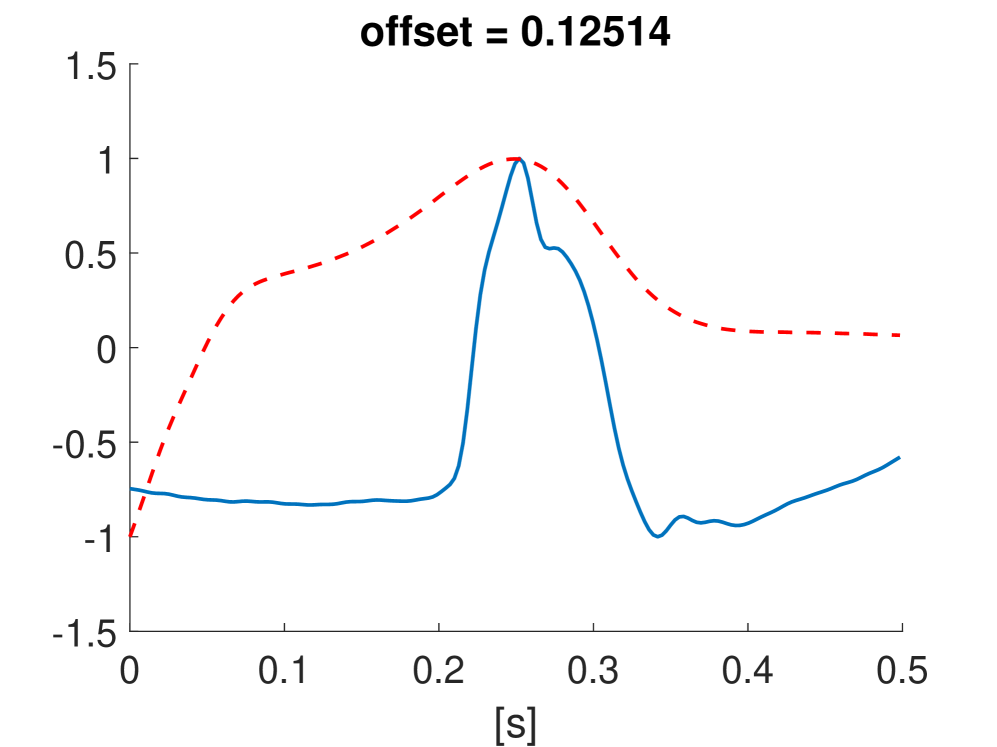

Besides the previous examples of latent space exploration for image datasets, kernel PCA is also applicable to other types of data. In this section, the MIT-BIH Arrhythmia dataset [19] is considered consisting out of ECG signals. The goal is to demonstrate the use of kernel PCA to extract interpretable directions in the latent feature space of the ECG signals.This would allow a clinical expert to gain insight and trust in the features extracted by the model. Similar research was previously done by [7] where they investigated the use of disentangled variational autoencoders to extract interpretable ECG embeddings. A similar approach is used to preprocess the data as in [7].

The signals from the patients with identifiers 101, 106, 103 and 105 are used for the normal beat signals and the data of patients 102, 104, 107, 217 for the paced beat signals. This results in a total of 785 beat patterns which are processed through a peak detection program [20]. The ECG signal is first passed through a fifth-order Butterworth bandpass filter with a lower cutoff frequency of 1Hz and upper cutoff frequency of 60Hz. The ECG beats are sampled at 360Hz and a window of 0.5 seconds is taken around each R-wave resulting in 180 samples per epoch. A regular Gaussian kernel with bandwidth is used, with . The first 10 principal components are used in the reconstruction.

In Fig. 9 the latent feature space projected on the first two principal components is shown. Kernel PCA is also able to separate between the normal and paced beats.

Fig. 10 shows the result in input space of moving along the first principal components in the latent feature space. As original base point we take a normal beat signal, i.e. corresponding to a hidden unit on the bottom right of Fig. 9(a). The smooth transition between the beat patterns allows for interpretation of the first principal components. This allows a clinical expert to understand on what basis the paced beats are separated by the principal components and if this basis has a physiological meaning. In order to investigate the separated region of the latent space at the top of Fig. 9(b) we start from a paced beat pattern and vary along the third principal component. This allows us to see which sort of heartbeat patterns are responsible for this specific distribution in the latent space.